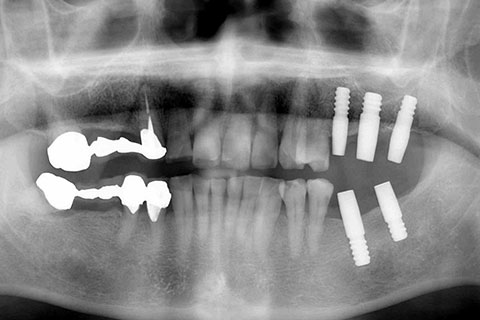

• 症例2

治療前

インプラント埋入時

治療後

年齢・性別

57歳男性

治療期間

3ヶ月

抜歯

なし

治療費

154万円

備考

左上5.6.7 及び左下6.7欠損

治療内容

左上5.6.7と左下6.7欠損部にインプラント埋入

施術の副作用(リスク)

オペによる知覚障害。インプラントによる歯肉炎。インプラント脱落。